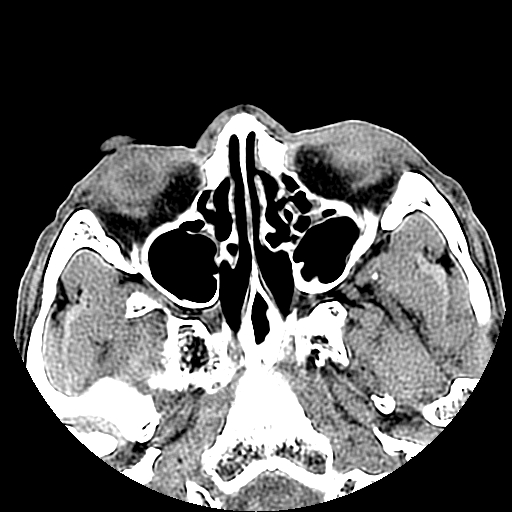

以下是引用liaoqiang在2008-7-16 21:15:00的发言:[br]右侧鼻骨骨折

以下是引用zxd95在2008-7-16 21:39:00的发言:[br]右侧上颌骨额突骨折。[br][br][br][br]